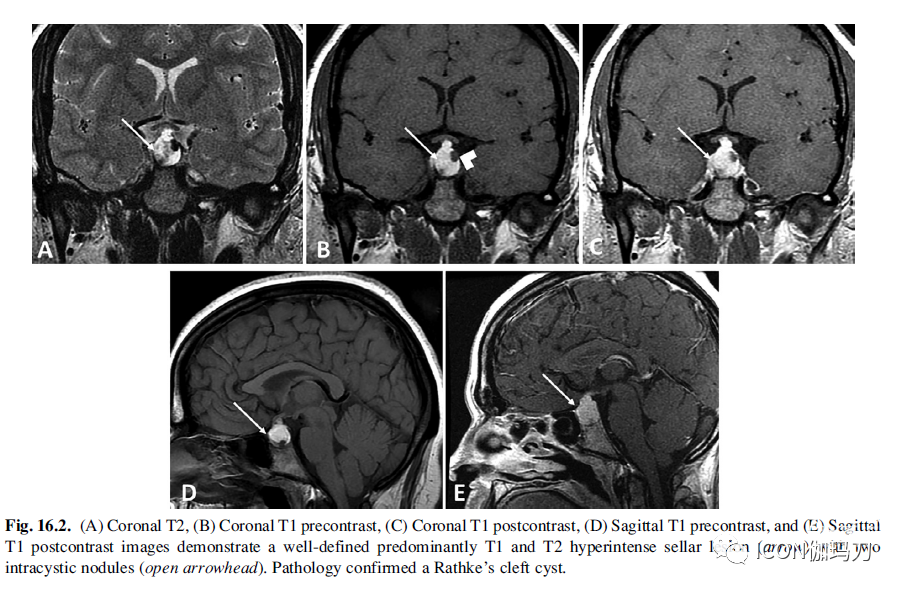

最常见的是,T1高信号,T2等低信号;然而,它们在T1和T2加权成像上显示出不同的信号强度,取决于囊内蛋白含量和存在囊内的结节(图16.2)。T1信号呈50%高信号,40%低信号,10%混合信号。T2信号70%为高信号,30%为等/低信号。75%的患者囊内结节T1高信号,T2低信号。囊肿和囊内结节没有钙化或强化,但很少表现为边缘强化。它们可能包含液-液水平面(fluid -fluid levels),但不常包含分隔(septations),这一特征有助于将其与囊性垂体腺瘤区分开来。受压的垂体周围无强化囊肿的强化边缘提示存在的爪征(a claw sign)。后壁征(The posterior ledge sign)是指囊肿向上延伸,穿过鞍膈和后叶上方的组织壁,这虽然不常见,但却是Rathke裂囊肿的特征。

图16.2.(A)冠状位T2, (B)冠状位T1平扫,(C)冠状位T1强化,(D)矢状位T1平扫,和(E)矢状位T1强化图像显示界限明确的T1和T2高信号鞍区病变(箭头),伴两个囊内结节(开放箭头)。病理证实为Rathke裂囊肿。